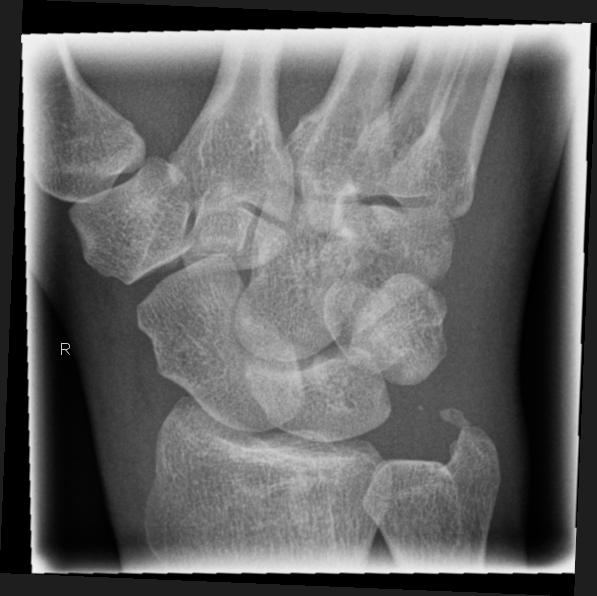

Os scaphoideum (Quartettaufnahme - Spezialaufnahme)

Technik

• FDA: 1,05 m

• Ausgangsformat: 10/10

• Übertischaufnahme

Lagerung

sitzend - seitlich zum Tisch

1.    Aufnahme

HG/Hand liegt flach auf

Hand kräftig bzw. so weit wie möglich zur Kleinfingerseite abduzieren

Daumen und Radius bilden eine Linie

2.    Aufnahme

15° Keil unter Bildempfänger

Lagerung siehe 1. Aufnahme

3.    Aufnahme

Unterarm und Hand an der radialen Seite um ca. 45° anheben

dabei ruhen die Finger auf der abfallenden Seite des kleinen 45° Keil

4.    Aufnahme

Unterarm und Hand an der ulnarer Seite um ca. 45° anheben

den Unterarm nicht anheben

dabei ruhen die Finger auf der aufsteigenden Fläche des kleinen 45° Keil

Zentralstrahl

1.- 4. Aufnahme

Längszentrierung: 1QF von der Hautgrenze zu den Handwurzelknochen

Querzentrierung: Kuhle distal von Proc. Styloideus radii

Einblendung

2QF in alle Richtungen

Bemerkung

Os scaphoideum: zwischen Daumensattelgelenk und Radius

Bei Kassette: es empfiehlt sich im Uhrzeigersinn auf der Kassette zu arbeiten.

Qualitätskriterien

Os scaphoideum soll orthograd überlagerungsfrei abgebildet sein, in den Schrägaufnahmen weitgehend überlagerungsfreie Darstellung des Os scaphoideum und der angrenzenden Handwurzelknochen. Schwer erkennbare Brüche sind oft nur in diesen Schrägaufnahmen diagnostizierbar.